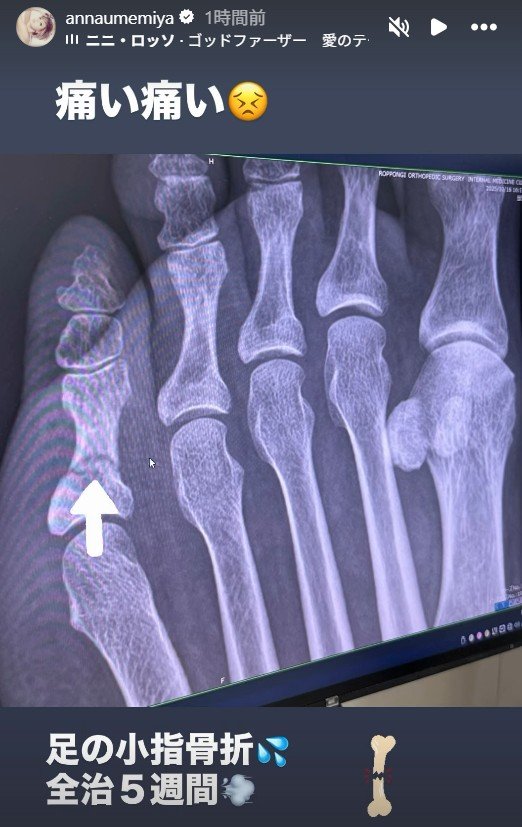

梅宮アンナさんは「痛い 痛い」と綴ると、レントゲンの画像をアップ。

続けて「足の小指骨折 全治5週間」と、状況を説明しています。